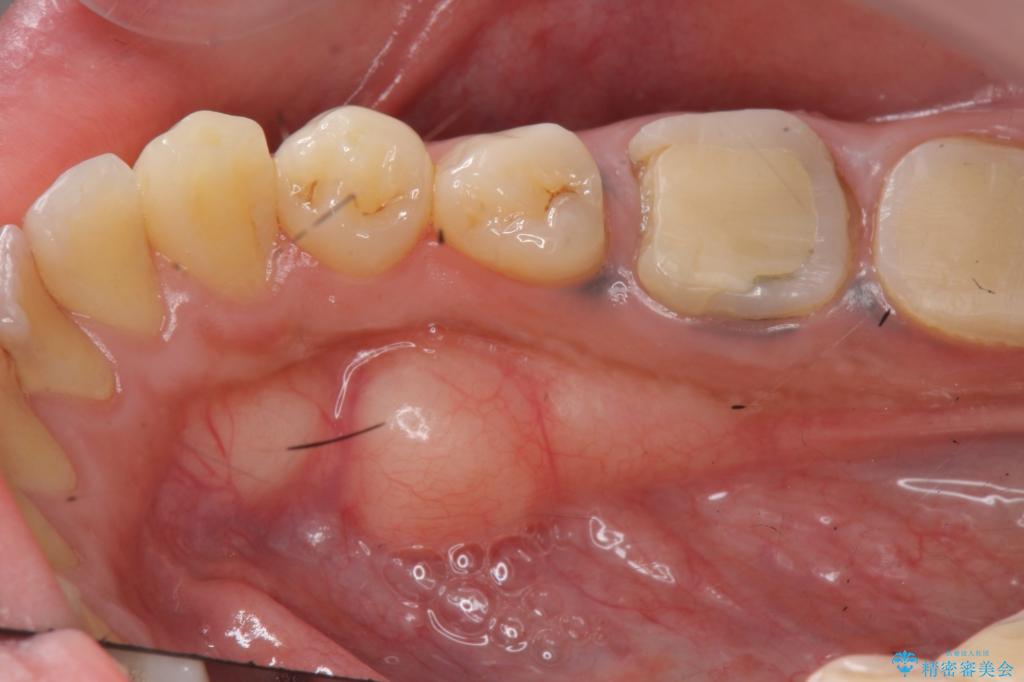

奥歯は既に根管治療が為されクラウンを装着する必要性がある状態ですが、歯の高さが低くクラウンの安定性・強度を担保するために歯周外科を行う治療計画としました。

歯周外科を行うことで、歯ぐきの位置を下げ歯の高さを作り出し安定したクラウンの装着が可能となります。また同時に舌の邪魔となっていた骨隆起の除去を行うこととしました。